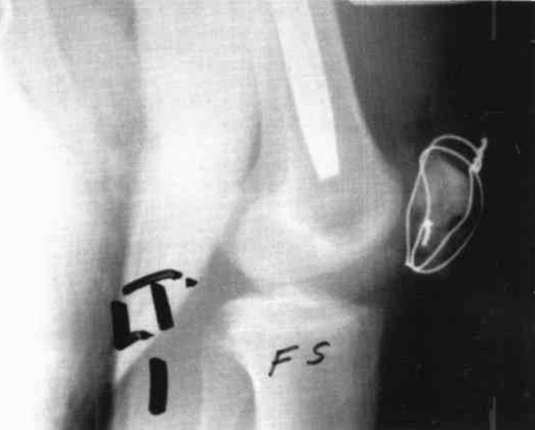

A nineteen year old male sustained a distal fracture with a split condylar fracture to the right leg (Fig. 10) and a lateral condyle fracture on the contralateral side (Fig. 11). Fractures were stabilized, but were not internally fixed at time of admission because of emergency vascular repairs being required. Three days post injury, the patient underwent ORIF of his fractures (Fig. 12 and Fig. 13). The right leg was placed in a free knee Mobilizing Brace and the left leg was placed in the rehabilitative free knee orthosis. A continuous passive motion dynamic suspension system was placed on the lower right extremity (Fig. 14). The lower left extremity had normal pain free motion following surgery. The patient was kept in passive motion for five days and achieved 0-100° of pain free motion. A cast brace was applied on the right extremity; the patient received gait training and was discharged.

Case 4